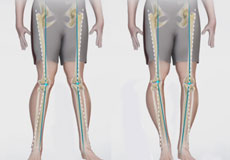

Bowed Legs

Bowed leg is a bony deformity resulting in outward curvature of one or both knees of the lower legs. It is commonly seen in toddlers and overweight adolescents.

Knocked Knees

Knock knees, also called genu valgum, is a type of angular knee deformity in which the legs curve inwards at the knees. It usually affects children in the age group of 3-4 years. The condition may correct itself as the child grows to the age of 7 to 8 years.

Knee Angular Deformities

Angular deformities of the knee are variations in the normal growth pattern during early childhood and are common during childhood.